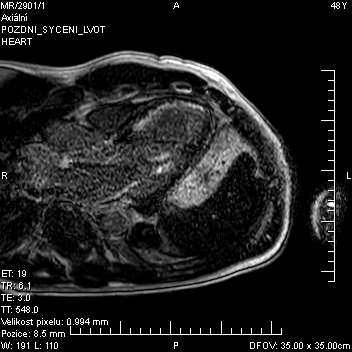

Pro podezření na myokarditidu pacient podstoupil z diferenciálnědiagnostických důvodů magnetickou rezonanci srdce (CMR) s nálezem vysoce suspektního subakutního infarktu myokardu v oblasti apexu, apikální poloviny interventrikulárního septa a inferoseptálně s typickým subendokardiálním ischemickým pozdním sycením, v mezidobí došlo ke zlepšení ejekční frakce levé komory na 50 % (obr. 1, 2, 3).

U pacientů hospitalizovaných pro akutní infarkt myokardu bez obstrukce koronárních tepen (myocardialinfarctionwith non-obstructivecoronaryarteries, MINOCA) se doporučuje provedení CMR po invazivní angiografii, pokud není konečná diagnóza jasná.8 Přínos CMR zde spočívá zejména v hodnocení tkáňové charakteristiky myokardu. U ischemického postižení nacházíme většinou přítomnost LGE v lokalizaci odpovídající infarktové tepně a vždy je postižena subendokardiální oblast.Nepřítomnost typického obrazu LGE ischemického postižení má velmi vysokou negativní prediktivní hodnotu (94 %) z hlediska vyloučení ischemické etiologie. Je nutno zdůraznit, že negativní nález při koronarografickémvyšetření nemusí vylučovat ischemickou etiologii kardiálního postižení, tak jako tomu bylo v našem případě.9 Lze shrnout, že kombinace normálního koronarografického nálezu s výsledkem CMR neprokazujícím ischemický typ LGE s velmi vysokou pravděpodobností odliší ischemickou a neischemickou etiologii kardiálního postižení.10